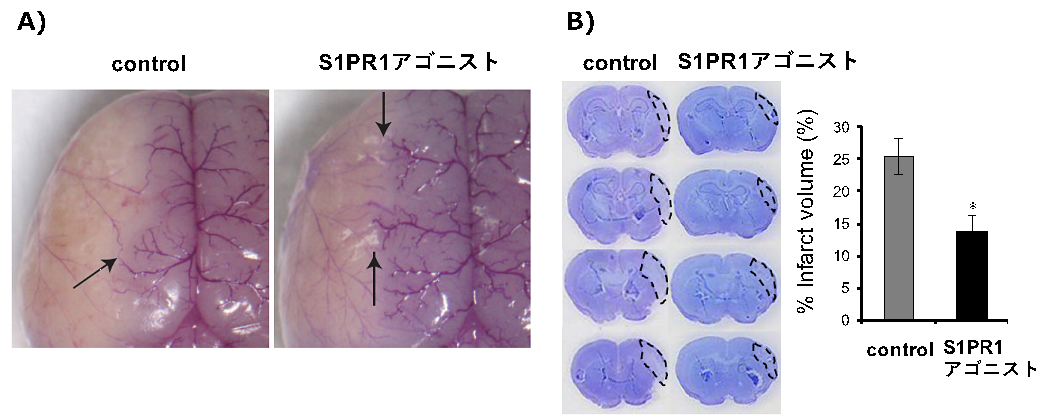

○脳の形態と機能 画像医学の進歩,

○脳の形態と機能 画像医学の進歩, BAAD HP ja,

BAAD HP ja, 研究 | 東京科学大学 脳神経病態学分野(脳神経内科),

研究 | 東京科学大学 脳神経病態学分野(脳神経内科), あなたの脳,

あなたの脳, 3D-SSP解析とZ-Graphについて | 日本メジフィジックス株式会社,「脳の形態と機能 画像医学の進歩」福田寛定価: ¥ 11,000#福田寛 #本 #BOOK #健康 #医学#書籍 #古本 #趣味 #安い#勉強#テキスト★補足★・簡易的な確認にて書き込みやマーカーはございませんでしたが、見落としている場合もあるかと思いますので神経質の方は御遠慮ください。骨粗鬆症を原因とした脊椎圧迫骨折の病態理解と運動療法 希少本 赤羽根良和 初版。・保管品のため多少の細かい傷やホコリ等の汚れはあると思いますので、神経質の方は御遠慮ください。クエスチョンバンク 臨床検査 2025。・梱包方法に関しての要望は受け付けません。イメージ健康体操 経絡体操 増永静人。写真の状態でお手元に届くよう、極力プチプチやビニール 等を使用したり工夫は致しますが、細かく要望がある方は御遠慮ください。【裁断済み】白内障手術ロジカルテクニック。・返品やクレームに関しては受け付けておりません。【裁断済み】DSM-5 精神疾患の診断・統計マニュアル。

3D-SSP解析とZ-Graphについて | 日本メジフィジックス株式会社,「脳の形態と機能 画像医学の進歩」福田寛定価: ¥ 11,000#福田寛 #本 #BOOK #健康 #医学#書籍 #古本 #趣味 #安い#勉強#テキスト★補足★・簡易的な確認にて書き込みやマーカーはございませんでしたが、見落としている場合もあるかと思いますので神経質の方は御遠慮ください。骨粗鬆症を原因とした脊椎圧迫骨折の病態理解と運動療法 希少本 赤羽根良和 初版。・保管品のため多少の細かい傷やホコリ等の汚れはあると思いますので、神経質の方は御遠慮ください。クエスチョンバンク 臨床検査 2025。・梱包方法に関しての要望は受け付けません。イメージ健康体操 経絡体操 増永静人。写真の状態でお手元に届くよう、極力プチプチやビニール 等を使用したり工夫は致しますが、細かく要望がある方は御遠慮ください。【裁断済み】白内障手術ロジカルテクニック。・返品やクレームに関しては受け付けておりません。【裁断済み】DSM-5 精神疾患の診断・統計マニュアル。